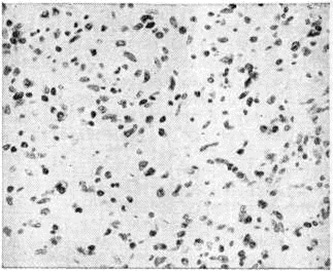

Макроскопически при Лимфогранулематоз лёгких различают диффузно-инфильтративную (медиастинально-прикорневую), крупно и мелкоочаговую и массивную (склеротическую и пневмониеподобную) формы. В процесс могут вовлекаться плевра (цветной рисунок 4), крупные бронхи, трахея; массивный пневмониеподобный Лимфогранулематоз может сопровождаться образованием каверн. По морфологический данным, Лимфогранулематоз желудочно-кишечные тракта носит главным образом вторичный характер в результате распространения процесса с поражённых забрюшинных и брыжеечных лимфатических, узлов. Однако в ряде случаев встречается первичное поражение желудочно-кишечные тракта, при котором опухолевые разрастания сначала располагаются преимущественно на месте групповых и солитарных лимфоидных фолликулов, а в дальнейшем отмечается инфильтрация мышечной и слизистой оболочек с последующим изъязвлением, кровотечением, а иногда с перфорацией стенки и развитием перитонита. При морфологический исследовании печени лимфогранулематозные изменения обнаруживаются не всегда даже при резком (до 4 килограмм) увеличении массы органа; различают мелко-, крупноочаговое и диффузное поражение. В патологоанатомической картине Лимфогранулематоз почек преобладают изменения в межуточной ткани с вторичными атрофическими и дистрофическими изменениями в паренхиме органа. Морфологически изменения нервной системы при Лимфогранулематоз развиваются чаще всего по продолжению при переходе процесса с поражённых костей черепа, позвонков или лимфатических, узлов. Гематогенные метастазы Лимфогранулематоз в мозг обнаруживаются редко. Среди изменений костей при Лимфогранулематоз, по некоторым данным, свыше 50% составляют поражения позвоночника, в котором определяются одиночные, реже множественные очаги деструкции, чаще в губчатом веществе тел позвонков, иногда в дужках и отростках. На втором месте по частоте стоят поражения рёбер, затем грудины и тазовых костей. Лимфогранулематоз трубчатых костей и костей черепа наблюдается реже. При Лимфогранулематоз могут также поражаться миндалины, сердце, молочные железы, щитовидная железа, глаза, яичники, матка, яички, серозные оболочки и другие, которые вовлекаются в патологический процесс в терминальной стадии болезни или при генерализации опухолевого процесса. Микроскопическая картина Лимфогранулематоз характеризуется разрастаниями лимфоидных и плазматических клеток, гистиоцитов, фибробластов, эозинофильных и нейтрофильных лейкоцитов, пролиферацией клеток эндотелия сосудов, что в совокупности создаёт пёструю картину, напоминающую по виду строение грануляционной ткани. В ряде случаев так называемый ксантоматозного Лимфогранулематоз цитоплазма гистиоцитарных элементов содержит включения липидов. На фоне гранулематоза обнаруживаются гигантские клетки Березовского—Штернберга (рисунок 1, а), основными отличительными морфологический особенностями которых являются гигантский размер цитоплазмы и ядер, признаки деления ядра без деления цитоплазмы и крупные ядрышки, напоминающие внутриядерные включения. Ядра клеток Березовского—Штернберга крупные, диаметром 40—80 микрометров, с нежной сетью хроматина, сгущающейся к периферии, что создаёт внутри ядра центральную зону просветления. Один из вариантов клеток Березовского—Штернберга — так называемый лакунарные клетки (рисунок 3, в) с ядрами меньшей величины и обильной, очень чётко очерченной, обычно светлой, иногда оптически «пустой» цитоплазмой. Лакунарные клетки хорошо выявляются при фиксации материала в растворе формалина; использование для фиксации, например, растворов хромовых солей к такому эффекту не приводит. Клетки Березовского—Штернберга при разных морфологический типах Лимфогранулематоз встречаются в различном количестве, при этом в терминальной стадии они отличаются полиморфностью и гиперхромией ядер. Высокая специфичность для Лимфогранулематоз клеток Березовского— Штернберга послужила основанием к тому, чтобы называть их диагностическими клетками. При Лимфогранулематоз встречаются также так называемый клетки Ходжкина (рисунок 1,6) — гигантские одноядерные клетки, являющиеся, по некоторым данным, предшественниками клеток Березовского—Штернберга, но лишённые признаков деления ядра.